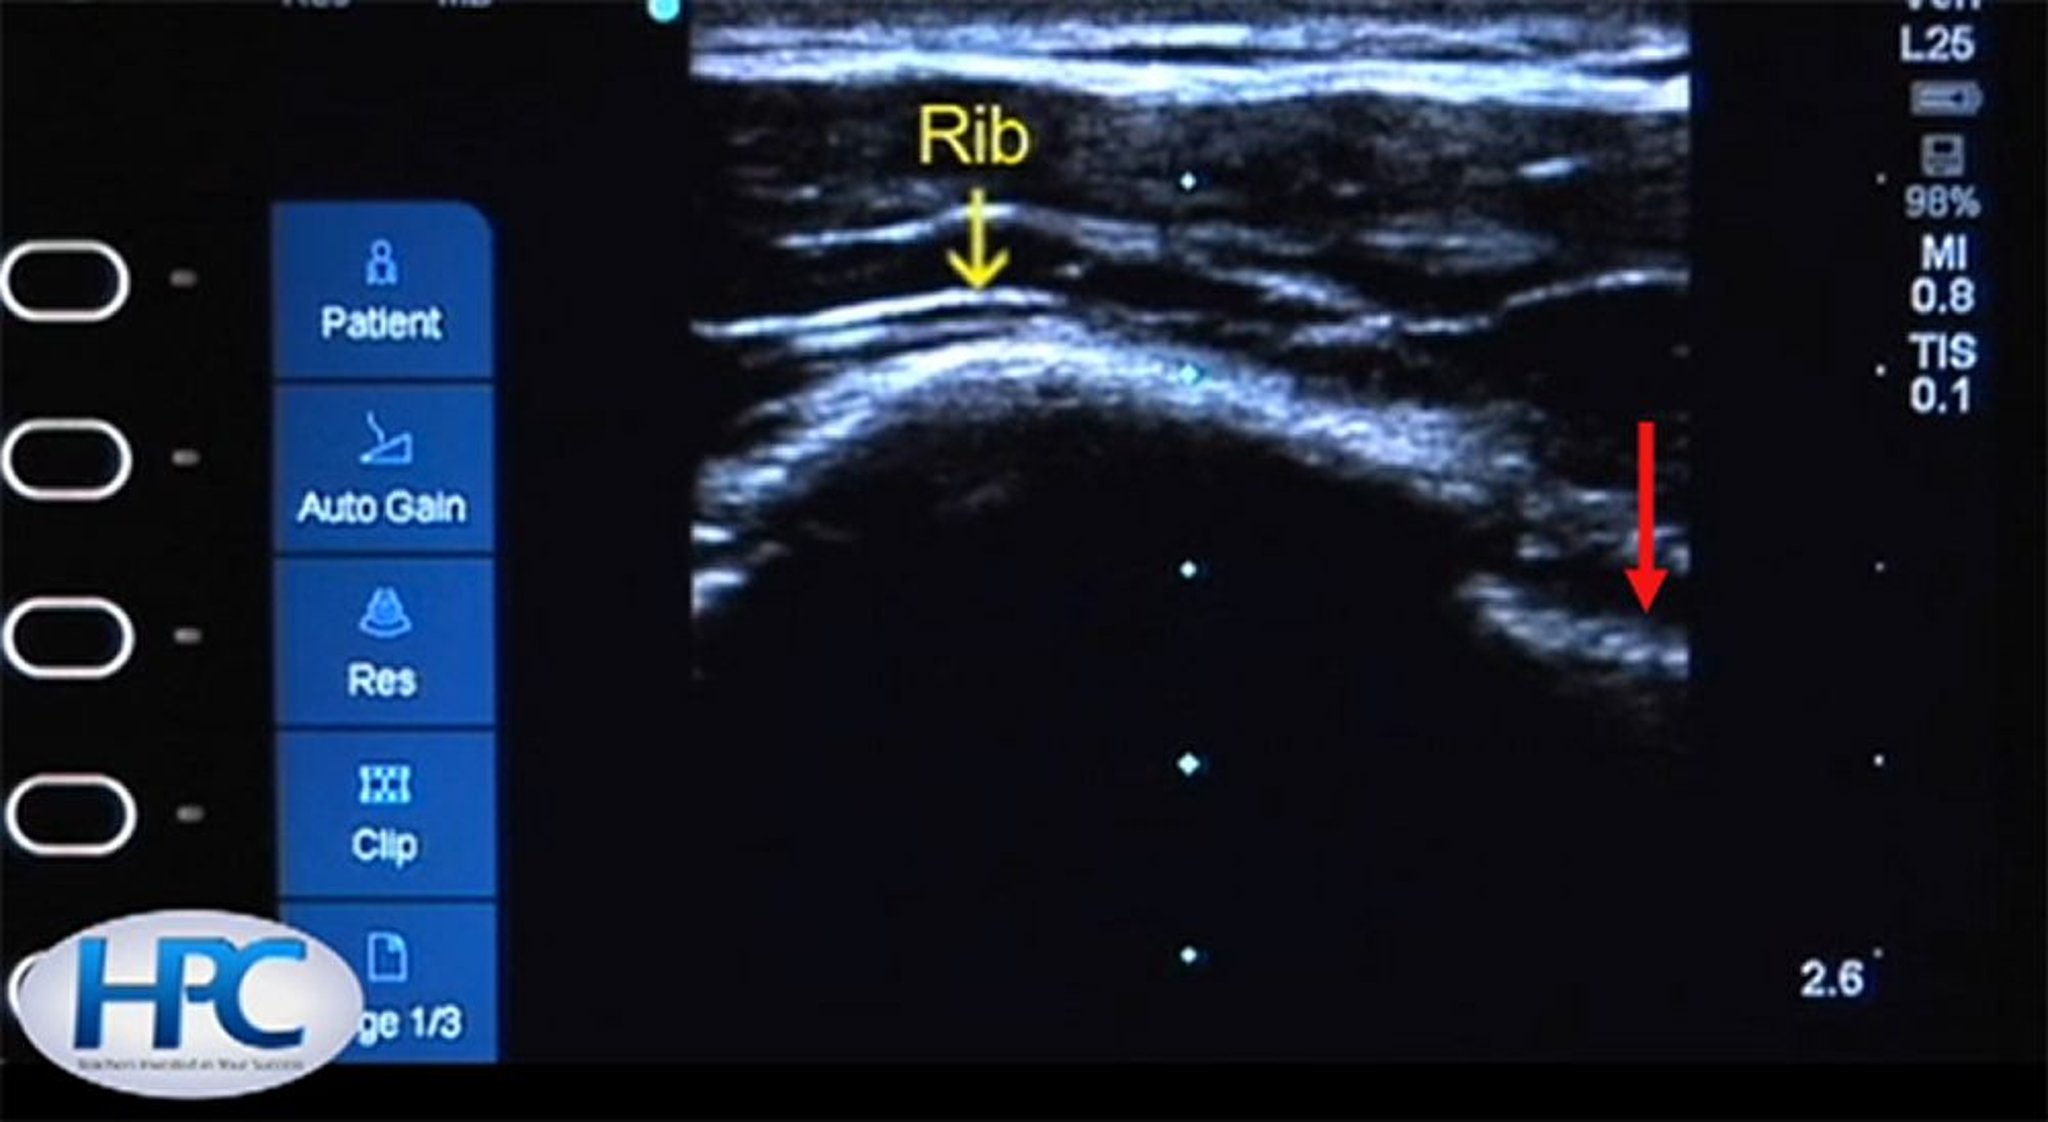

Hình ảnh siêu âm của xương sườn và đường màng phổi

Xương sườn (mũi tên màu vàng) xuất hiện dưới dạng cấu trúc âm tăng (màu trắng) có bóng mờ bên dưới xương sườn. Đường màng phổi (mũi tên màu đỏ) hiện rõ ở khoang liên sườn.